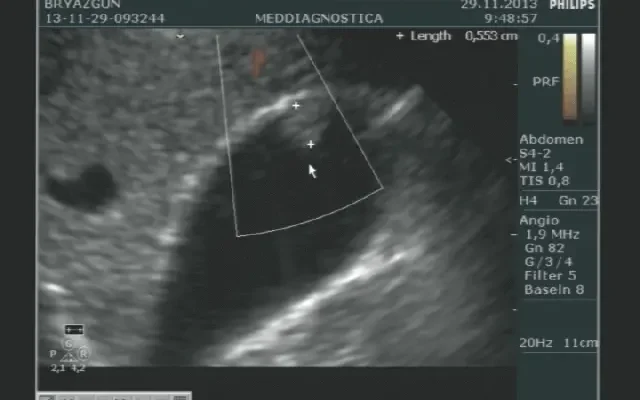

Чому лікарі такі суворі? УЗД черевної порожнини — не просто модна назва для процедури. Це спосіб побачити, що приховано під шкірою. І всьо через звичайний ультразвук. Отже, усі ваші сніданки, кава та перекуси можуть створити ускладнення. І не тому, що у шлунку застрягає гречка чи йогурт. Просто зайві бульбашки і рідина приховують справжнє кіно нутрощів! Ультразвук не бачить крізь них. Тож, якщо хочете ясної картинки — утримайтесь від їжі за кілька годин до процедури.

Кофеїн. Оце диво-привид. Не лише пробуджує зранку, але й заставляє кишківник працювати так, що аж гуркоче. Це може влаштувати свого роду свято у вашій черевній порожнині, змушуючи її блищати на УЗД. Хтось може і зрадіє, але це нечіткі зображення. Ну, ласкава відмова від цієї радості хоча б на одну мить перед УЗД — це вже замах на щастя.

От ви і без кави, сідаєте, міцелярка, оператор із датчиком… Відчуття, ніби тваринку привели в ультразвукову уяву. Кава могла б розслабити, але треба витримки. Пульс, бухання, сите кашище всередині. І якщо кава все-таки у животику, ехо ехіватаємість збільшується. Вона там пляскає як маленька яхта на великих хвилях. На жаль, таку картину не розгледіти.